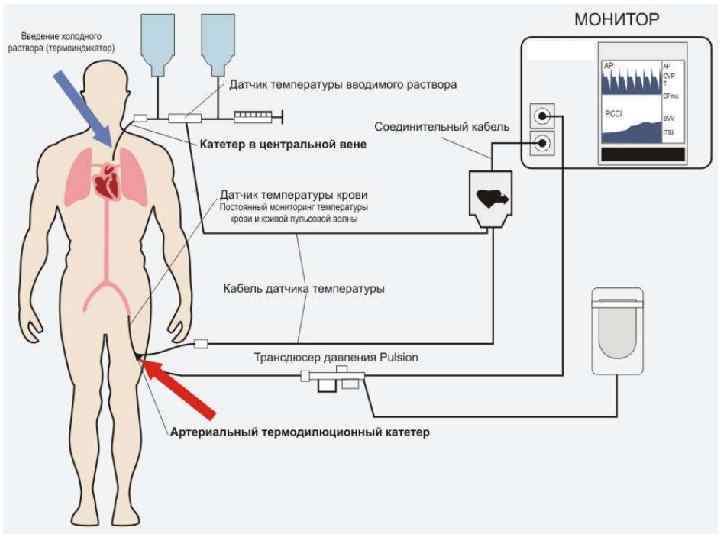

Дилюционные методы Наиболее точные количественные методы

Дилюционные методы Наиболее точные количественные методы